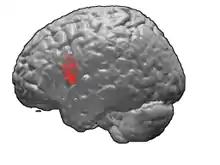

Anatomists such as Paul Broca were able to associate behavioral defects with structural damage to particular parts of the brain. The part of the brain called "Broca's area" was linked to disruption of speech generation without any block in the ability of patients to comprehend language. Broca's area is connected to nearby parts of the brain that contain cells with axons that carry movement control signals to the spinal cord. The bundles of movement control axons degenerate and are smaller than normal in patients with Lou Gehrig's disease.

About a decade after Broca's area was recognized as a movement control area of the brain, Vladimir Betz used a new technique, the Golgi stain, to identify a type of giant pyramidal shaped cells that are movement control cells of the brain. These "Betz cells" are among the largest neurons of the human brain and they are depleted from the brains of patients with Lou Gehrig's disease.